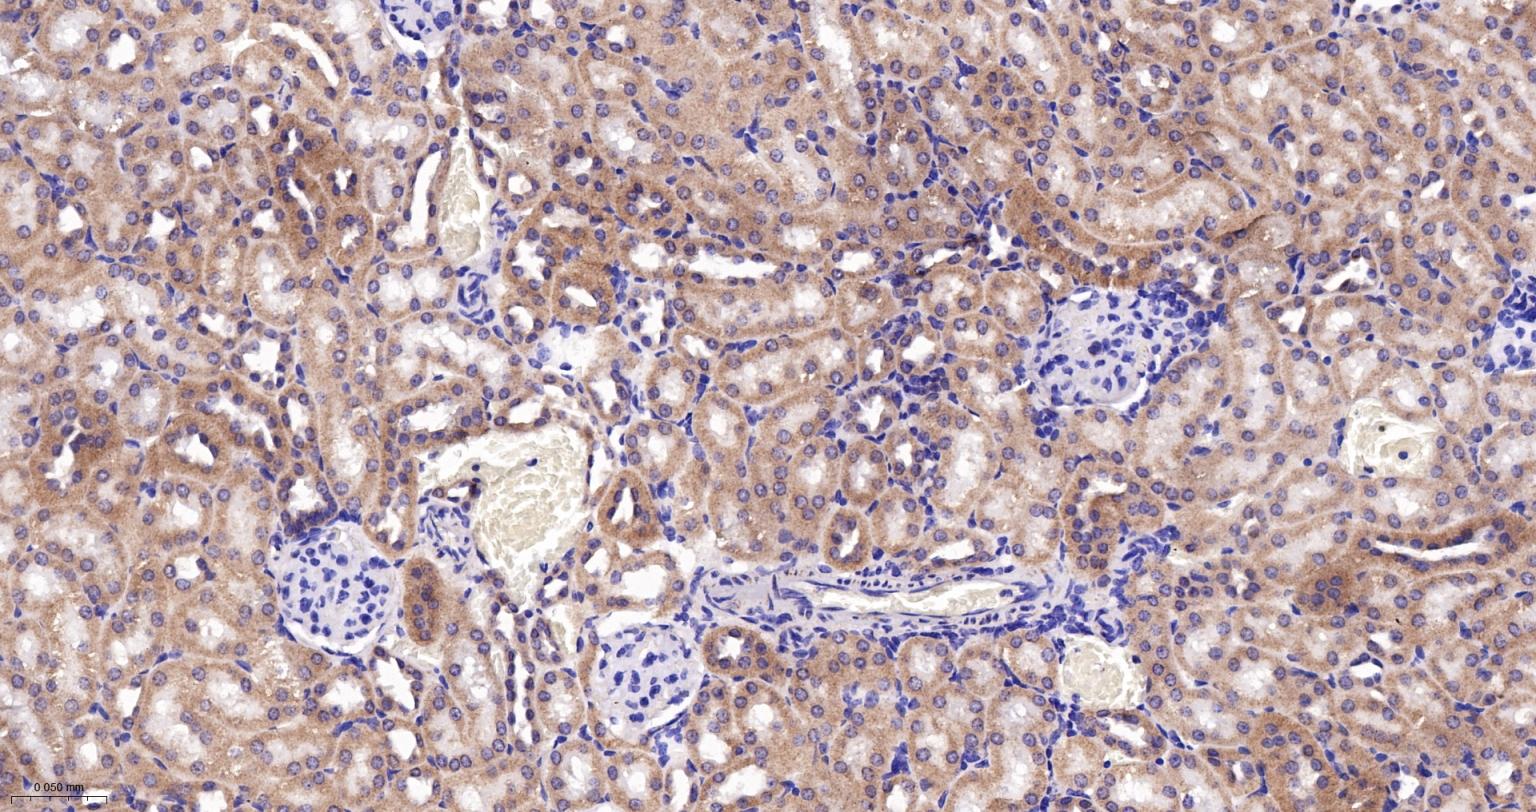

Paraformaldehyde-fixed, paraffin embedded Rat Kidney; Antigen retrieval by boiling in sodium citrate buffer (pH6.0) for 15 min; The section was incubated with ATP5MC1 Monoclonal Antibody, Unconjugated (bsm-61256R) at 1:200 overnight at 4°C, followed by conjugation to the bs-0295G-HRP and DAB (C-0010) staining.

Paraformaldehyde-fixed, paraffin embedded Mouse Kidney; Antigen retrieval by boiling in sodium citrate buffer (pH6.0) for 15 min; The section was incubated with ATP5MC1 Monoclonal Antibody, Unconjugated (bsm-61256R) at 1:200 overnight at 4°C, followed by conjugation to the bs-0295G-HRP and DAB (C-0010) staining.